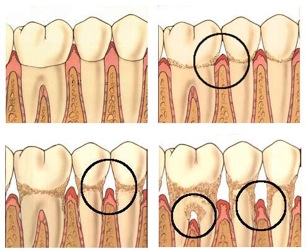

ENFERMEDAD PERIODONTAL

Unas encías sanas determinan que los dientes estén bien sujetos y firmes para poder cumplir su función. La enfermedad que afecta a las encías se determina enfermedad periodontal(o piorrea) y consta de 2 etapas:

- GINGIVITIS

Aparece una inflamación, enrojecimiento y sangrado espontáneo de las encías, provocado por la acumulación de placa bacteriana, que produce toxinas que irritan el tejido gingival. También se puede acompañar de halitosis o mal sabor de boca. El hueso y el tejido conectivo que sostiene los dientes aún no ha sido dañado. Es el momento de consultar a su dentista y solucionar el problema.

- PERIODONTITIS

Se forman unas bolsas debajo del borde de las encías donde se acumula la placa bacteriana. El hueso se reabsorbe y las fibras que sostienen a los dientes se dañan. Si se abandona y no se cuida la periodontitis avanza, comienza la movilidad dental y puede llegar a perder sus dientes. La salud de sus encías esta relacionada con su bienestar y salud general. La existencia de infecciones periodontales se relaciona con un mayor riesgo de sufrir enfermedades cerebrovasculares y cardiovasculares, especialmente infarto de miocardio, problemas respiratorios, diabetes, complicaciones en el nacimiento (bebés prematuros y bajos de peso).